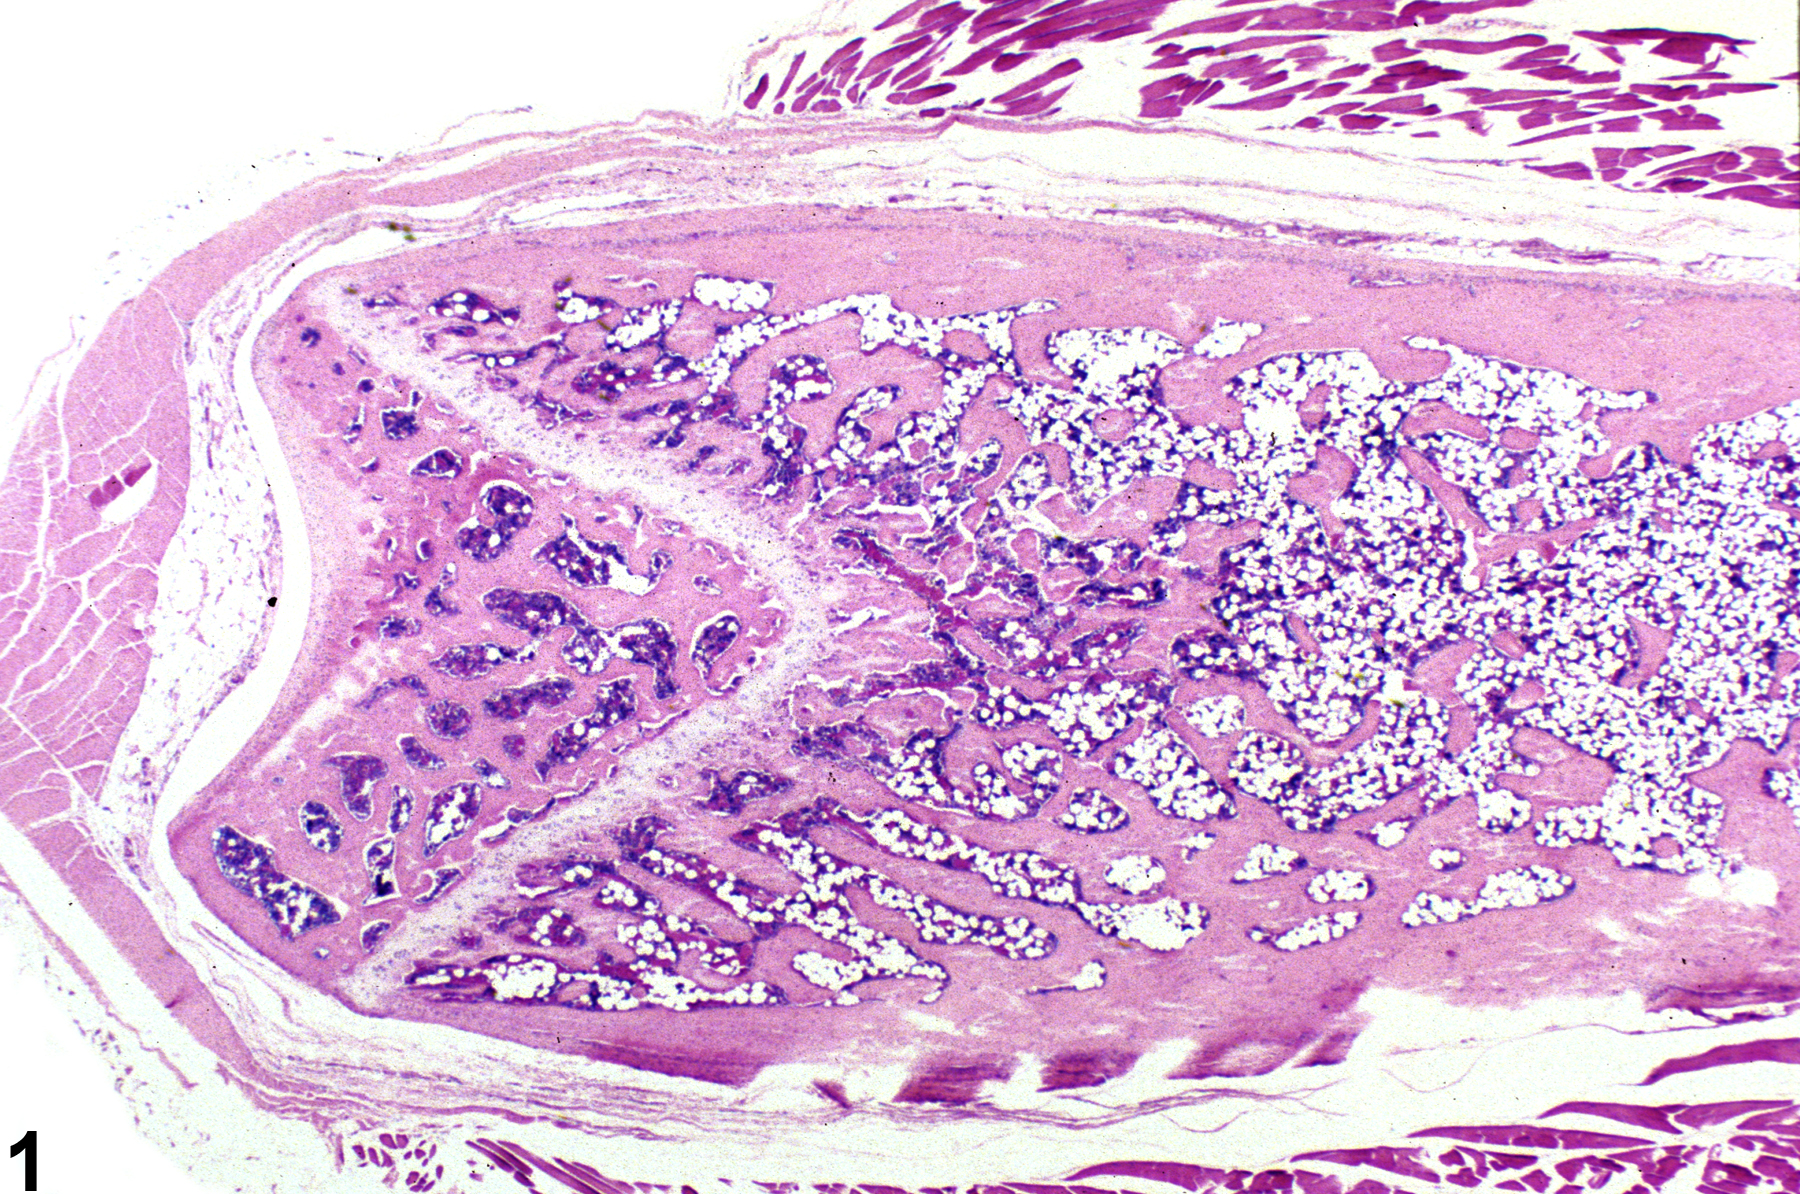

Hypercellularity of the bone marrow is recorded in treated animals when there is an increase in hematopoietic cells relative to adipocytes compared with concurrent controls (Figure 2, Figure 4, and Figure 5). Hypercellularity may occur as a nonspecific or direct (e.g., with cytokine administration) response to compound administration but more commonly is due to a regenerative response as a consequence of decreases in peripheral blood cells, recovery from a xenobiotic-induced bone marrow injury, or inflammation. For example, hypercellularity may be secondary to sepsis or a result of blood loss, hemolytic anemia or platelet consumption/destruction. Stimulation to produce more of one cell line can cause increased production of other cell lines, causing an overall increase in bone marrow cellularity. With marked hypercellularity, hematopoietic cells may fill the entire marrow space, even extending through the nutrient foramina.

Bone marrow in a control female F344 rat from a subchronic study.